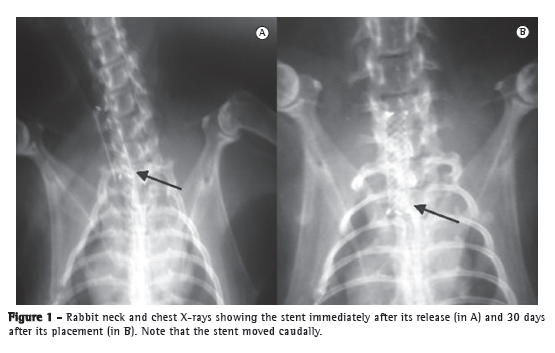

Stent migration was observed in 5 of 6 animals (84%). Of the 13 animals that survived the observation period, 7 had rigor mortis, which precluded hyperextension of the neck for X-ray examination and, consequently, the determination of the exact position of the stents. Therefore, stent migration was analyzed in the 6 remaining animals only. Covered and self-expanding stents have been reported to show high migration rates, our results being therefore consistent with those reported in the literature (Figure 1).(6,7)

We determined the degree of expansion by measuring the external diameter of the stents. We found that the stents expanded in 100% of the cases, expansion having been complete in 54% and nearly complete in 46%. This small difference can be attributed to the size of the stent, which is purposely larger than the trachea so that fixation can occur by radial force.